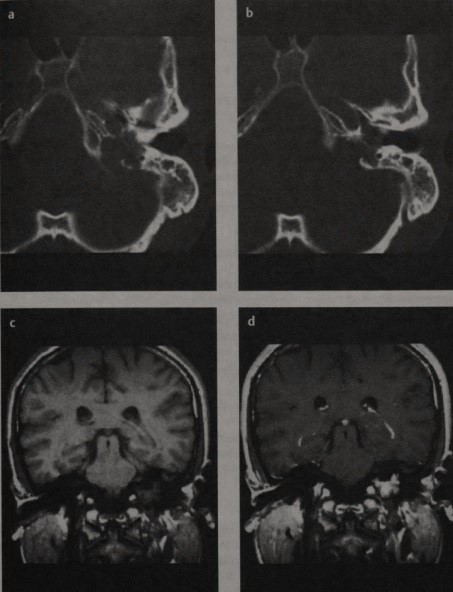

Другим распространенным заболеванием височной кости является холестероловая гранулема, которая чаще всего образуется на верхушке пирамид височных костей с хорошей пневматизацией. В этом месте содержимое воздухоносных ячеек часто не может нормально опорожниться, из-за чего на их месте появляется медленно увеличивающееся в размерах образование, при отсутствии лечения способное разрушать окружающие ткани. Из-за высокого содержания воды и наличия продуктов распада холестероловые гранулемы выглядят яркими на Т1 и Т2.

(а) Т1 МРТ с гадолинием, фронтальный срез. Холестероловая гранулема, распространяющаяся из сосцевидного отростка в левую височную долю (стрелка).

(б) МРТ в аксиальной проекции в режиме Т2. Обратите внимание на то, что сигнал повышен и на Т1, и на Т2 (стрелка).